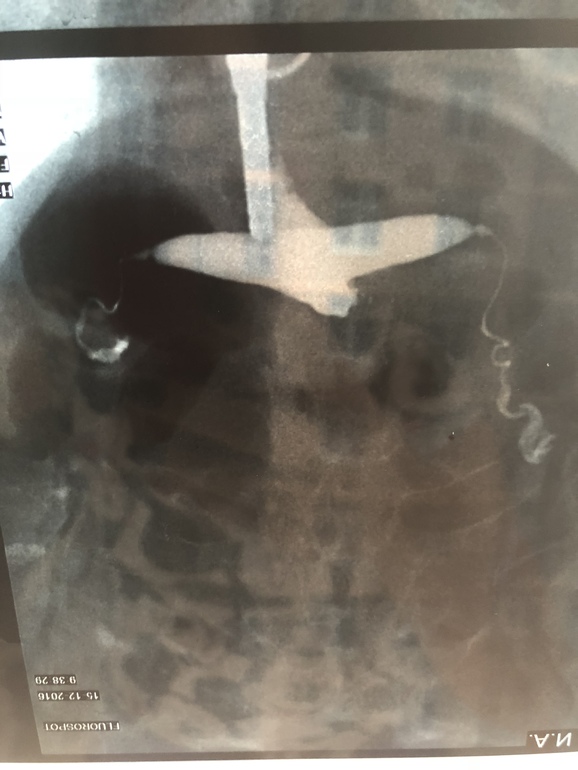

Сегодня была у врача в другой клинике, пришла на УЗИ, с полным перечнем документов и сказала, что хочу вторую попытку ВМИ. Врач посмотрел анализы, УЗИ, мрт и попросил снимок труб. По снимку сказал, у вас выход только один, ЭКО. Сказать, что я была в шоке, не сказать ничего. Ещё и муж уезжает надолго в командировку. У меня есть результат метросальпингографии в котором написано «заключение : полость матки седловидной формы, контуры четкие, ровные, отклонена кзади. Правая маточная труба визуализируеься на всём протяжении, несколько извитая, выход контраста свободный. Левая маточная труба визуализируется на всём протяжении, выход контраста свободный.»

Сказал что трубы сужены и через них не проходит яйцеклетка, ВМИ может только привести к внематочной беременности, и разрыву трубы. И выход только один, ЭКО.

Мои трубы смотрели огромное количество врачей, напротажении с декабря 2016 года и никто, ни один врач, не говорил что трубы слишком заужены. Столько времени утрачено...